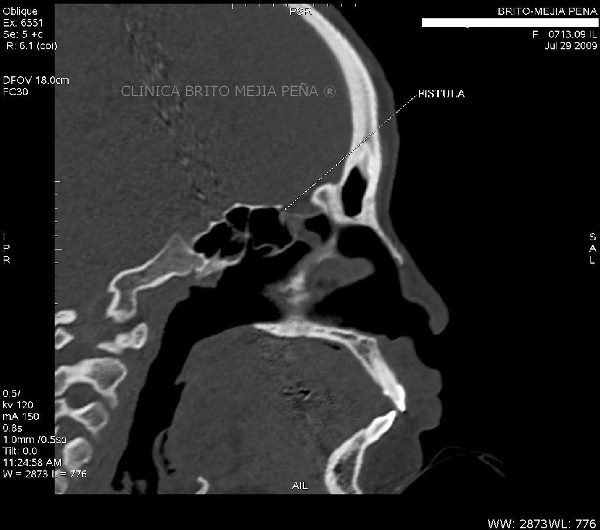

Fístula LCR sagital